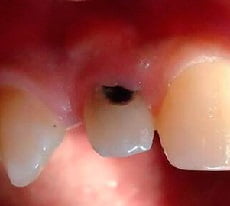

Пришеечный кариес: фото до и после

Как выглядит данный тип кариеса, предлагаем к просмотру подробные фото зуба.